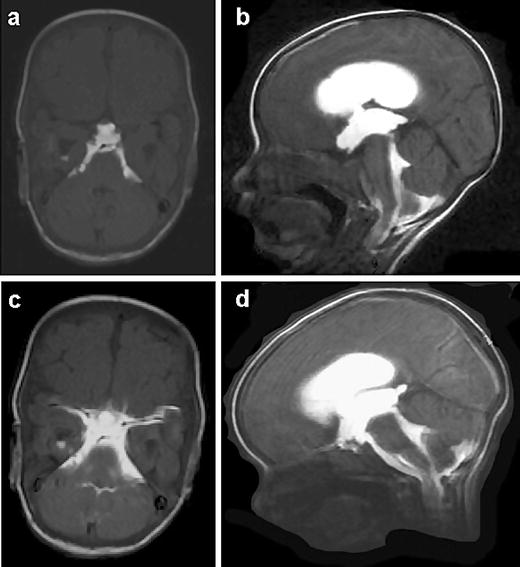

Combined endoscopic third ventriculostomy and choroid plexus

From cure.org

Combined endoscopic third ventriculostomy and choroid plexus Endoscopic Ventriculostomy Learn about the indications, advantages, complications, and technical principles of endoscopic third ventriculostomy (etv), a minimally invasive procedure for hydrocephalus. Endoscopic third ventriculostomy is a surgical procedure used to treat children and adults diagnosed with obstructive or non. Endoscopic third ventriculostomy (etv) offers a durable surgical option for patients. Summarize the proper technique in regards to. A ventriculostomy is a. Endoscopic Ventriculostomy.

Figure 1 from Combined Endoscopic Third Ventriculostomy and Endoscopic Ventriculostomy Learn about the healthcare team, the anesthesia, the surgery, and the recovery process from this web page. Etv surgery is a brain procedure that creates a hole in the floor of the third ventricle to allow cerebrospinal fluid (csf) to flow and bypass the obstruction. Endoscopic third ventriculostomy is a surgical procedure used to treat children and adults diagnosed with. Endoscopic Ventriculostomy.